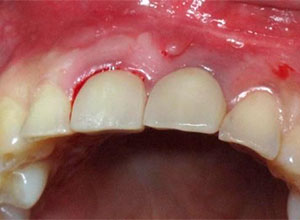

Al término de la distracción dejamos pasar tres meses con una férula en acrílico. En el diente 21 que habíamos visto en la radiografía un problema de un absceso periapical y periodontal.

Sindesmotomía del tejido

Extracción, limpieza y curetaje del alveolo

Poste direccional del implante

Radiografía del poste de guía

Material osteogénico en masa

Sutura y reconstrucción del tejido blando papilar